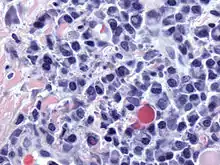

Плазматичні клітини — це великі лімфоцити з великою кількістю базофільної цитоплазми і характерним виглядом під час світлової мікроскопії. Вони мають ексцентричне ядро з гетерохроматином у характерному розташуванні колеса або циферблата. Їх цитоплазма також містить бліду зону, яка на електронній мікроскопії містить розгалужений апарат Гольджі та центріолі (ЕМ-фото). Розгалужений ендоплазматичний ретикулум поєднанні з добре розвиненим апаратом Гольджі робить плазматичні клітини добре пристосованими до секреції імуноглобулінів.[4] Інші органели плазматичної клітини включають рибосоми, лізосоми, мітохондрії та плазматичну мембрану.